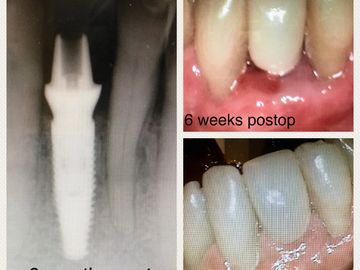

upper lateral with "hybrid abut" titanium base, zirc pillar, then cemented zirc crown.

custom abut replaced immed load temp lower anterior

Universal Abutment 4.5 diameter x 2.5mm ging margin